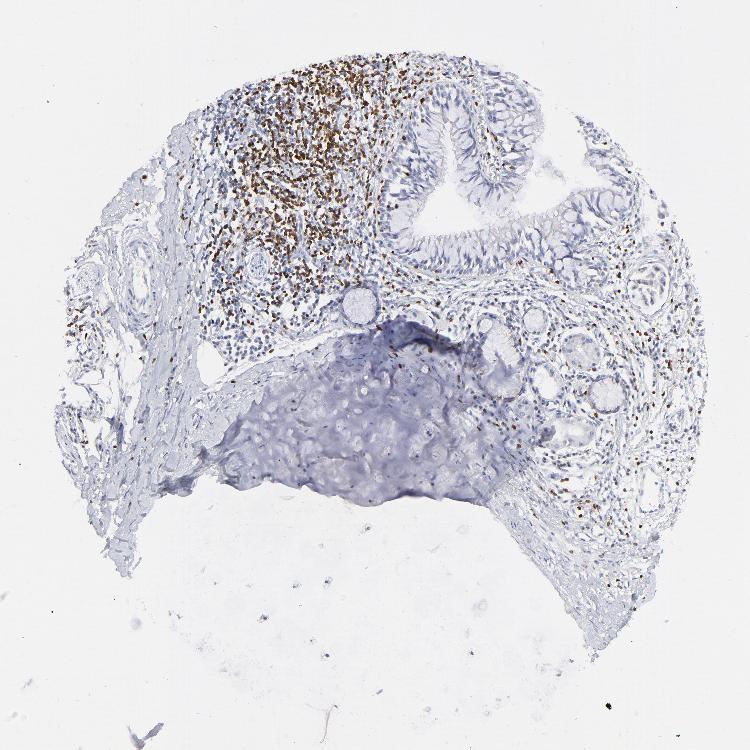

SOFT TISSUE 1 - Antibody stainingi

Antibody staining in the annotated cell types in the current human tissue is reported as not detected, low, medium, or high, based on conventional immunohistochemistry profiling in selected tissues. This score is based on the combination of the staining intensity and fraction of stained cells.

Each image is clickable and will lead to virtual microscopy that enables deeper exploration of all samples and also displays staining intensity scores, fraction scores and subcellular localization as well as patient and tissue information for each sample.

Antibody HPA003134Antibody CAB002625

Chondrocytes Not detectedNot detected

Fibroblasts Not detectedNot detected

Peripheral nerve Not detected-